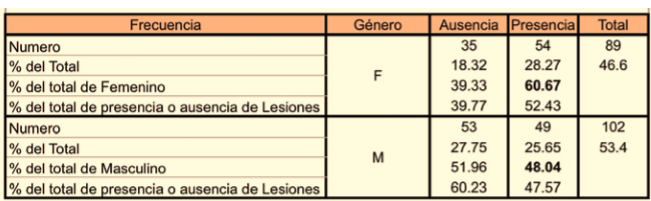

Considerando el género del sujeto los datos de la muestra indicaron que el 60,67% de las niñas presentaron algún tipo de lesión, mientras que para los niños esta proporción fue del 48,04%. La diferencia no fue significativa a un nivel del 5% (Chi-cuadrado = 3.0539, p = 0.0805) (TABLA 1).